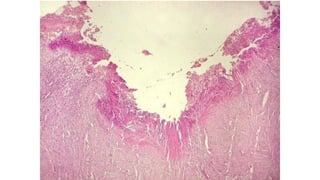

ULCERA PEPTICA

• Necrosis

glandular

• Exudado

inflamatorio

• crónico

ULCERA PEPTICA • Necrosis glandular •Exudado inflamatorio • crónico